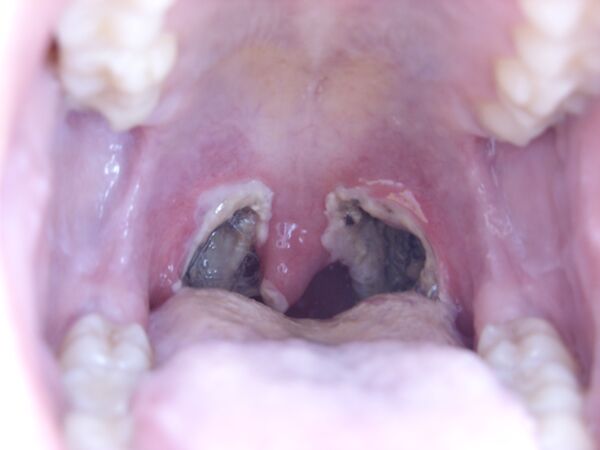

Тонзиллэктомия

Тонзиллэктоми́я (от лат. tonsilla — миндалевидная железа и греч. εκτομή — иссечение, удаление) — известная более 3000 лет хирургическая операция по полному удалению нёбных миндалин вместе с соединительно-тканной капсулой[1]. Выполняется при рецидивах острого тонзиллита или аденоидита, носовых обструкциях дыхательных путей, апноэ, храпе и паратонзиллярном абсцессе. До настоящего времени остаётся одним из наиболее распространённых оперативных вмешательств.

Галерея